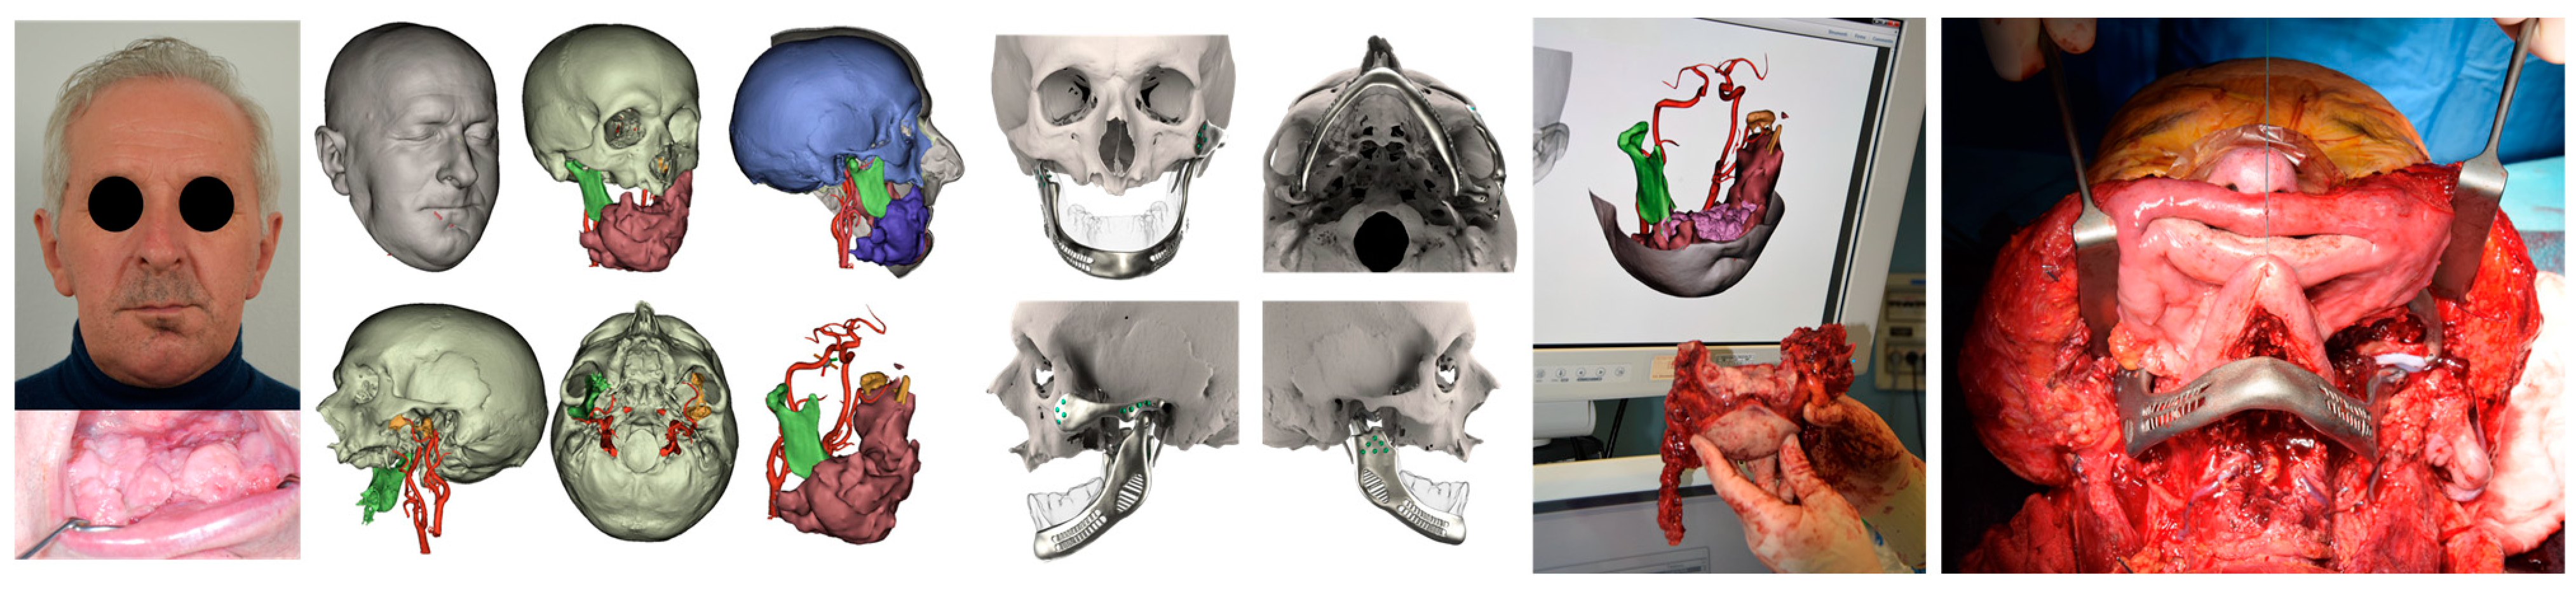

| ID | Age | Gender | Diagnosis | Complications | eTMJR Class | MIO before Surgery | MIO after Surgery | VAS Preoperatory | VAS at 6 Months | Follow-Up |

|---|---|---|---|---|---|---|---|---|---|---|

| 1 | 71 | Female | Ossifying fibroma o right temporal bone | None | FT-M0 | 29 mm | 35 mm | 2 | 0 | 5 years |

| 2 | 58 | Male | Left condylar osteoma | Partial left facial palsy | FA-M0 | 20 mm | 32 mm | 7 | 2 | 5 years |

| 3 | 41 | Male | Sarcomatoid carcinoma of lef hemimandible | None | F0-M3 * | 35 mm | 35 mm | 4 | 3 | 1 year |

| 4 | 71 | Male | High grade Mucoepidermoid carcinoma of the oral pelvis | Periprocedural pulmonary infection, Partial left facial palsy | FA-M3 | 27 mm | 30 mm | 7 | 5 | 4 years |

| 5 | 26 | Male | Bilateral severe TMJ ankylosis | None | FA-M0 | 8 mm | 24 mm | 8 | 1 | 4 years |

| 6 | 54 | Female | Left mandibular angle odontogenic keratocyst | None | F0-M2 | 36 mm | 38 mm | 5 | 3 | 3 years |

| 7 | 63 | Female | Infiltrating squamous cell carcinoma of the left cheek mucosa | Loss of the implant | F0-M3 | 23 mm | 34 mm | 5 | 2 | 2 years |

| 8 | 24 | Male | Right hemifacial fibrous dysplasia | None | F0-M3 * | 24 mm | 31 mm | 3 | 0 | 1 year |

| 9 | 52 | Female | Left articular eminence osteoblastoma | None | FT-M0 | 10 mm | 33 mm | 7 | 1 | 8 months |